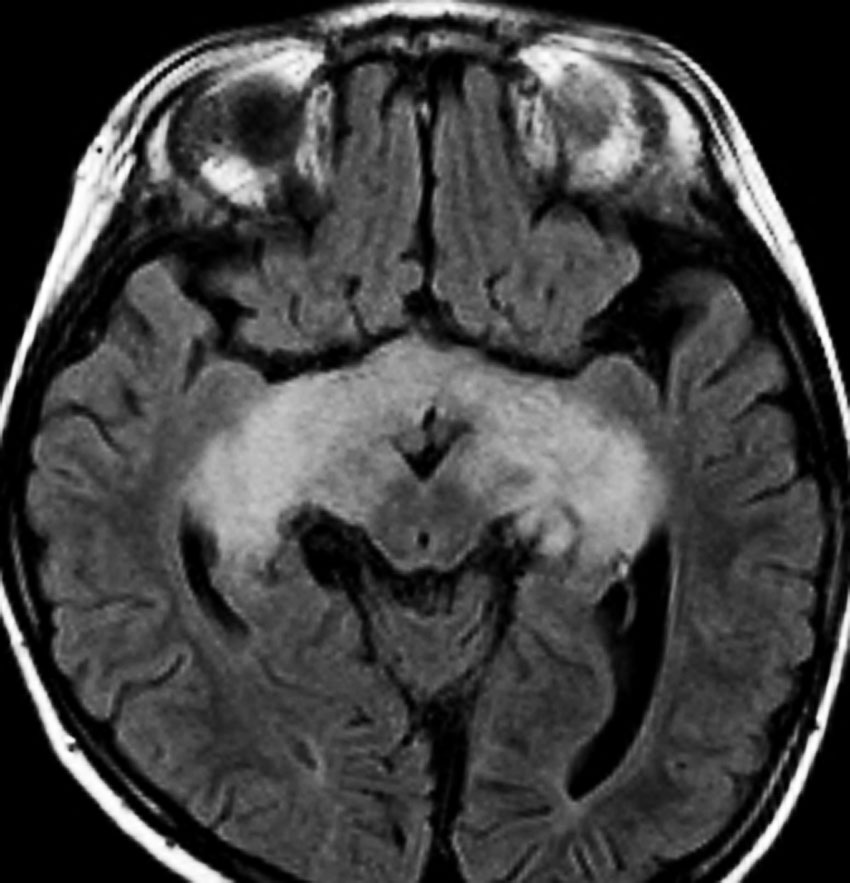

幼児の視路の毛様粘液性星細胞腫です。T2強調画像(左側)で白く高信号に写るのが特徴です。ガドリニウム増強ではまだらになっていますが,均一に真っ白に高信号になることも多いです。乳幼児のものは,ドロドロに柔らかい腫瘍です。

whole optic pathway pilocytic astrocytomaとは

両側の眼窩内視神経から視交叉、視索,外側膝状体,内包後脚,視放線近位部までが腫瘍化しています。FLAIRで高信号で,不規則にガドリニウム増強されます。これを手術摘出したり生検したりしても無駄です。放射線治療は不可能であり治療方法は化学療法のみです。

生後7カ月の幼児です。目が揺れるようになり(振り子様眼振)眼科を受診して腫瘍が発見されました。小児脳腫瘍の治療ができる病院へと紹介されました。

1ヶ月後にまたMRI検査がされました。乳児ですから検査にも麻酔が必要です。腫瘍は明らかに大きくなっています。左視神経から視索の腫瘍化が著しいので右側だけかすかに視力が残っているかもしれません。視力は明かりがわかる程度(明暗弁)と評価されました。